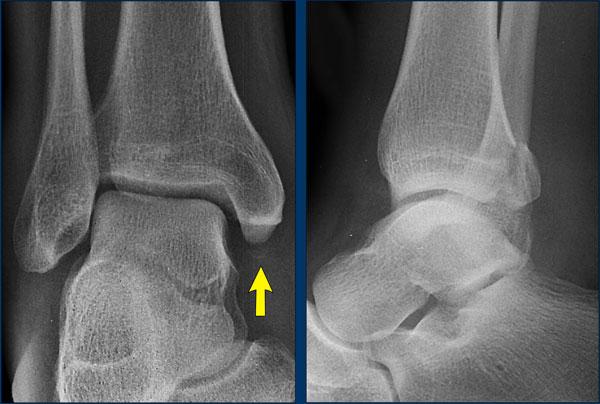

case 1 – distortion

The findings are:

- gãy xương thẳng đứng của mắt cá trong (mũi tên vàng).

Đây không phải là gãy xương do giật hay kéo, mà là gãy xương do đẩy. - Có thể có một avulsion của mắt cá ngoài (mũi tên trắng), nhưng điều đó chưa chắc chắn.

Tuy nhiên điều này không quan trọng vì chúng tôi sẽ trình bày ngay sau đây.

Gãy dọc mắt cá trong là gãy do lực đẩy.

Theo Lauge-Hansen, gãy xương xảy ra do lực khép trên bàn chân sấp.

Phía bên ngoài chịu lực căng cực độ với sự kéo giãn trên dây chằng bên ngoài.

Trong giai đoạn 1, có thể xảy ra đứt dây chằng bên ngoài hoặc gãy xương bong điểm bám (còn được gọi là Weber A).

Trong giai đoạn 2 luôn có gãy xương thẳng đứng của mắt cá trong và phải có hoặc là bong điểm bám của mắt cá ngoài hoặc đứt dây chằng bên vì các trình tự này luôn theo thứ tự này với giai đoạn 1 trước rồi đến giai đoạn 2.

Điều này có nghĩa là, dù chúng ta có thấy gãy xương ở phía bên ngoài hay không thì cũng không quan trọng.

Chắc chắn phải có tổn thương ở cả phía trong lẫn phía ngoài và chúng ta hiện biết rằng cổ chân không ổn định, vì vòng ổn định đã bị phá vỡ ở hai vị trí.

Here another unstable ankle fracture.

Theo Lauge-Hansen đây là giai đoạn SA 2.

Theo Weber đây là Weber A với gãy xương thêm ở mắt cá trong.